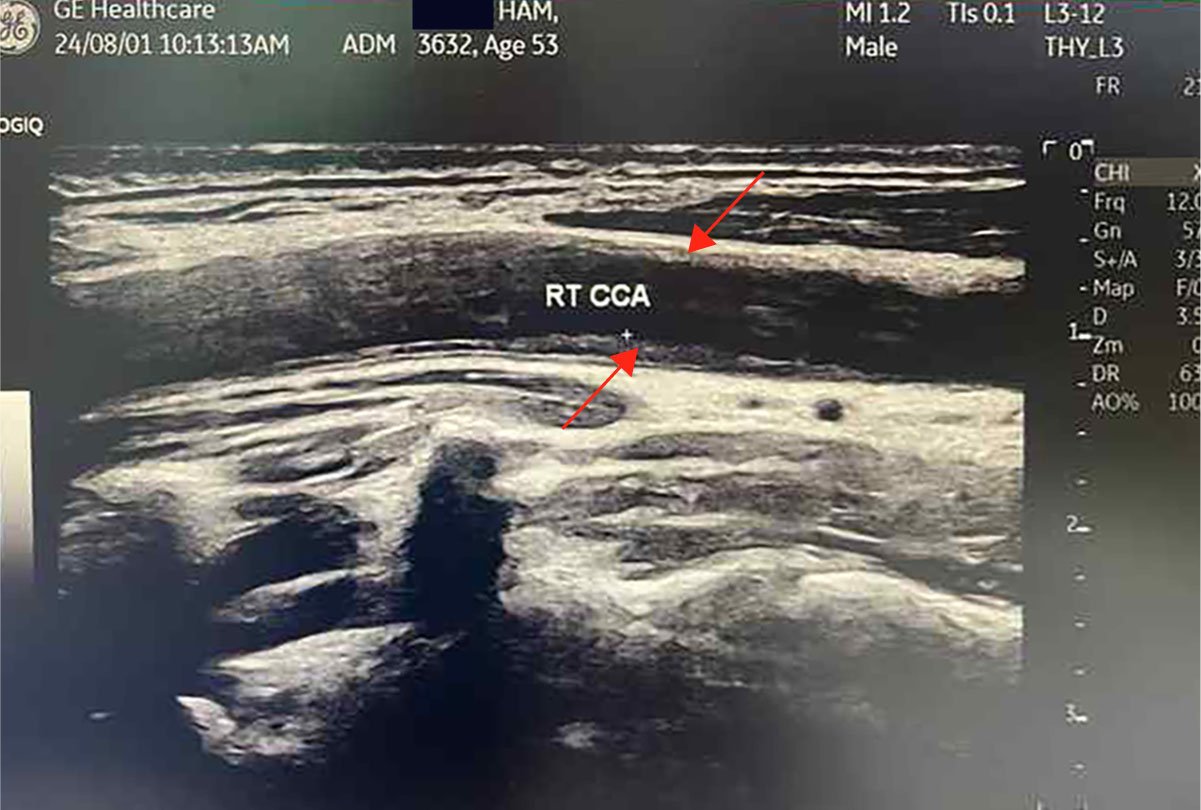

29% Carotid IMT

1.3mm → 0.99mm

0 mm3 Dangerous Plaque

LDNC eliminated